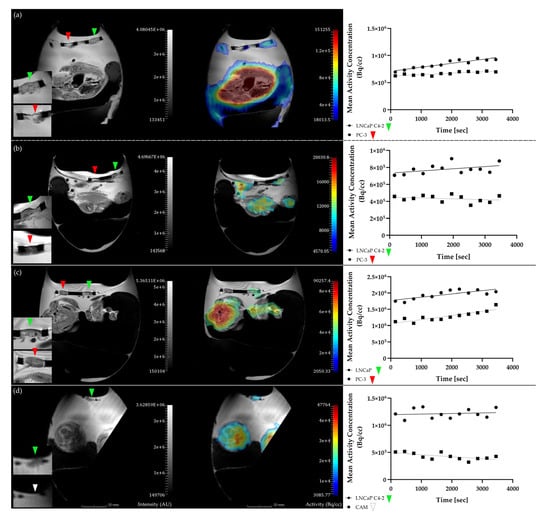

2.2. In Ovo MR and PET Imaging